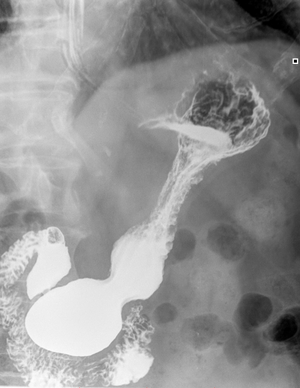

Современные технологии в медицине: рентгенодиагностика заболеваний желудка